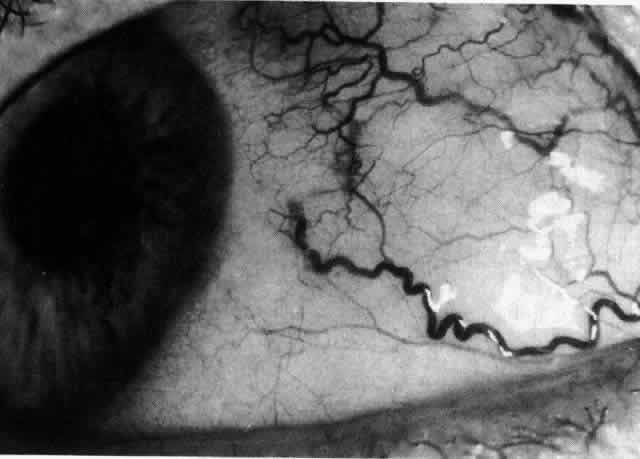

Simple and nodular episcleritis differ in their clinical courses, but in both the edema and infiltration are entirely within the episcleral tissues. The sclera is not involved. The maximum congestion is in the superficial episcleral network, with some slight congestion of the conjunctival vessels and deep episcleral vessels (Fig. 10). The intraocular structures are not involved in either variety, nor is the visual acuity affected. Anterior segment fluorescein angiography reveals a normal vascular pattern but a very rapid flow rate, with the whole transit of the dye being completed within 2 or 3 seconds (Figs. 11 and 12).

Fig. 11. Anterior segment fluorescein angiogram of a 45-year-old woman with simple episcleritis. At first transit of dye, all the vessels are dilated and filling simultaneously. However, the vascular pattern is not disturbed.

Fig. 12. Angiogram of the same 45-year-old woman in Figure 11 one second later. Within 1 second, all the vessels are filled and there is even, venular filling except in the deep episcleral plexus. This is the rapid filling pattern seen in all forms of episcleritis and in diffuse anterior scleritis.